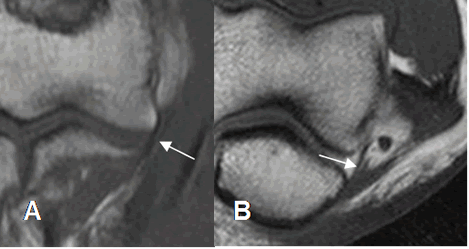

Existen 2 variantes normales, que no deben confundirse con patología en la RM. El seudodefecto del capitel y el seudodefecto del surco troclear. (8).

El seudodefecto del capitel se observa en la parte externa. Se valora en cortes axiales y debe tener bordes lisos, sin alteración en la señal de intensidad. Debe diferenciarse de fracturas, lesiones osteocondrales y quistes. (Fig 7 y 8).

Fig 8. Lesión osteocondral

A: Rx AP. Osteopenia difusa por artritis reumatoidea, con disminución de los espacios articulares.

B: RM coronal en T1 y C: RM coronal en STIR. Lesión osteocondral del epicóndilo lateral, con erosión y alteración de la señal.